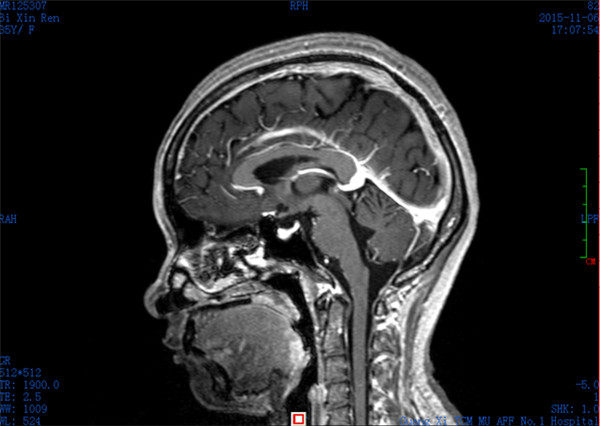

经与患者及家属充分沟通并获得同意后,外六科脑血管病介入治疗团队立即为患者行全脑血管造影,造影结果证实上矢状窦血栓形成,整个上矢状窦完全闭塞,若不采取措施病情很快就会恶化。再次征得家属同意后果断采取微导管介入手术治疗,手术在起病后当晚开始,由于患者血栓位置深在,需要经动、静脉双重途径置管,技术难度较大。术者选取Solitaire支架( 美国 公司)置入微导管远端,释放支架并在原位作短暂停留使支架与血栓充分接触并黏附,一起回撤支架与微导管取出血栓,手术一直持续到第二天凌晨。术后留置导管一条,用于每天以药物继续溶栓。术后患者即清醒,头痛明显缓解,无神经功能缺失。手术第二周时患者已经能够生活自理。2015年12月12日患者痊愈出院。

术后上矢状窦恢复通畅

病人治愈出院